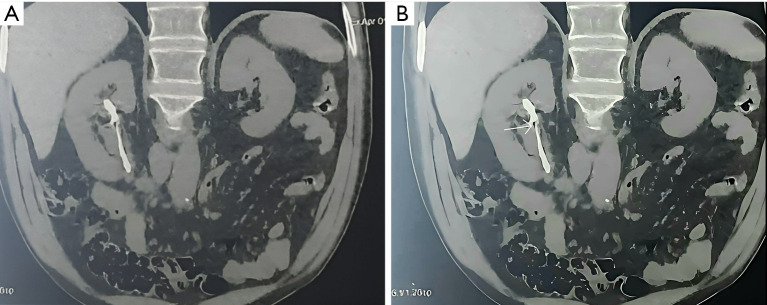

Case description: We present the case of a 64-year-old male patient from Casablanca with no notable medical history who reported right low back pain without accompanying fever and exhibited signs of a deteriorating general condition. Clinical examination revealed tenderness upon palpation of the right flank and a left thyroid nodule. Ultimately, a diagnosis of RPF secondary to prolonged occupational asbestos exposure was established. The patient underwent the insertion of a right JJ stent and received combined corticosteroid therapy.

Abstract Image